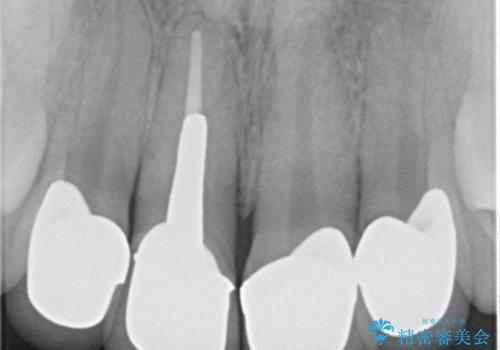

- 前歯のクラウンの見た目が不自然、歯の根元が見えたり金属色が気になるので改善したい、とセラミック治療を希望され来院されました。

歯肉の位置変化による審美障害を改善するため、オールセラミックジルコニアクラウンで再治療を行い審美性の改善を計画します。